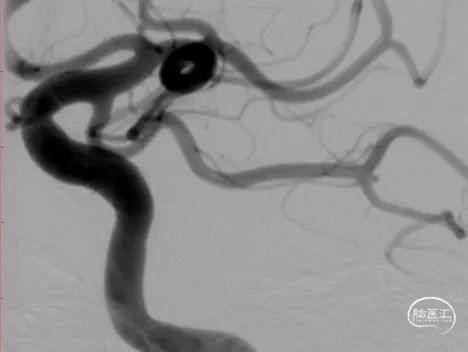

DSA结果:右侧颈内动脉后交通段动脉瘤, 7.2mm*6.7mm*5.7mm,瘤体上多个小子囊,载瘤动脉异常扭曲及不规则狭窄,直径约4.2mm。

术前DSA、DSA 3D

该病例为右侧后交通段绝对宽颈动脉瘤,动脉瘤体7.2mm*6.7mm*5.7mm,瘤体上多个小子囊,载瘤动脉异常扭曲,直径约4.2mm,工作角度难以选择;另外患者高龄,颈内动脉扭曲且不规则狭窄,因此对支架导管的输送性和支架的贴壁性要求较高。且患者动脉瘤存在多个小子囊,填塞后子囊不显影才能降低再出血风险。手术策略是三导管技术(两根弹簧圈微导管分别放入子囊和大的瘤腔、一根支架导管)。